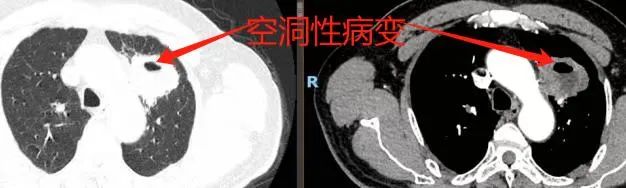

入院时胸部增强CT

入院后,胸部CT平扫发现其左肺上叶尖后段存在空洞性病变,进一步的胸部增强CT提示肺脓肿可能,给予抗炎、化痰输液治疗,然而患者症状改善并不明显。为明确病因,行支气管镜检查。检查中发现病变处支气管通畅,但黏膜充血、水肿,管腔内有大量脓痰。抽吸干净后,未发现新生物及明显狭窄,同时进行了活检和肺泡灌洗。令人欣慰的是,术后患者咳嗽、咳痰症状明显减轻,但活检病理检查却未见明显异常,患者好转出院建议每两月行胸部CT复查。